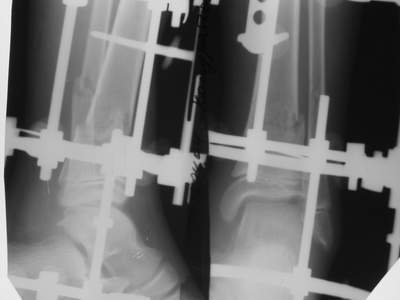

Так как речь зашла непосредственно о травме, см этапные

снимки. Как все было

Первичные

Вытяжение

Фиксация

в гипсе

Промежуточный